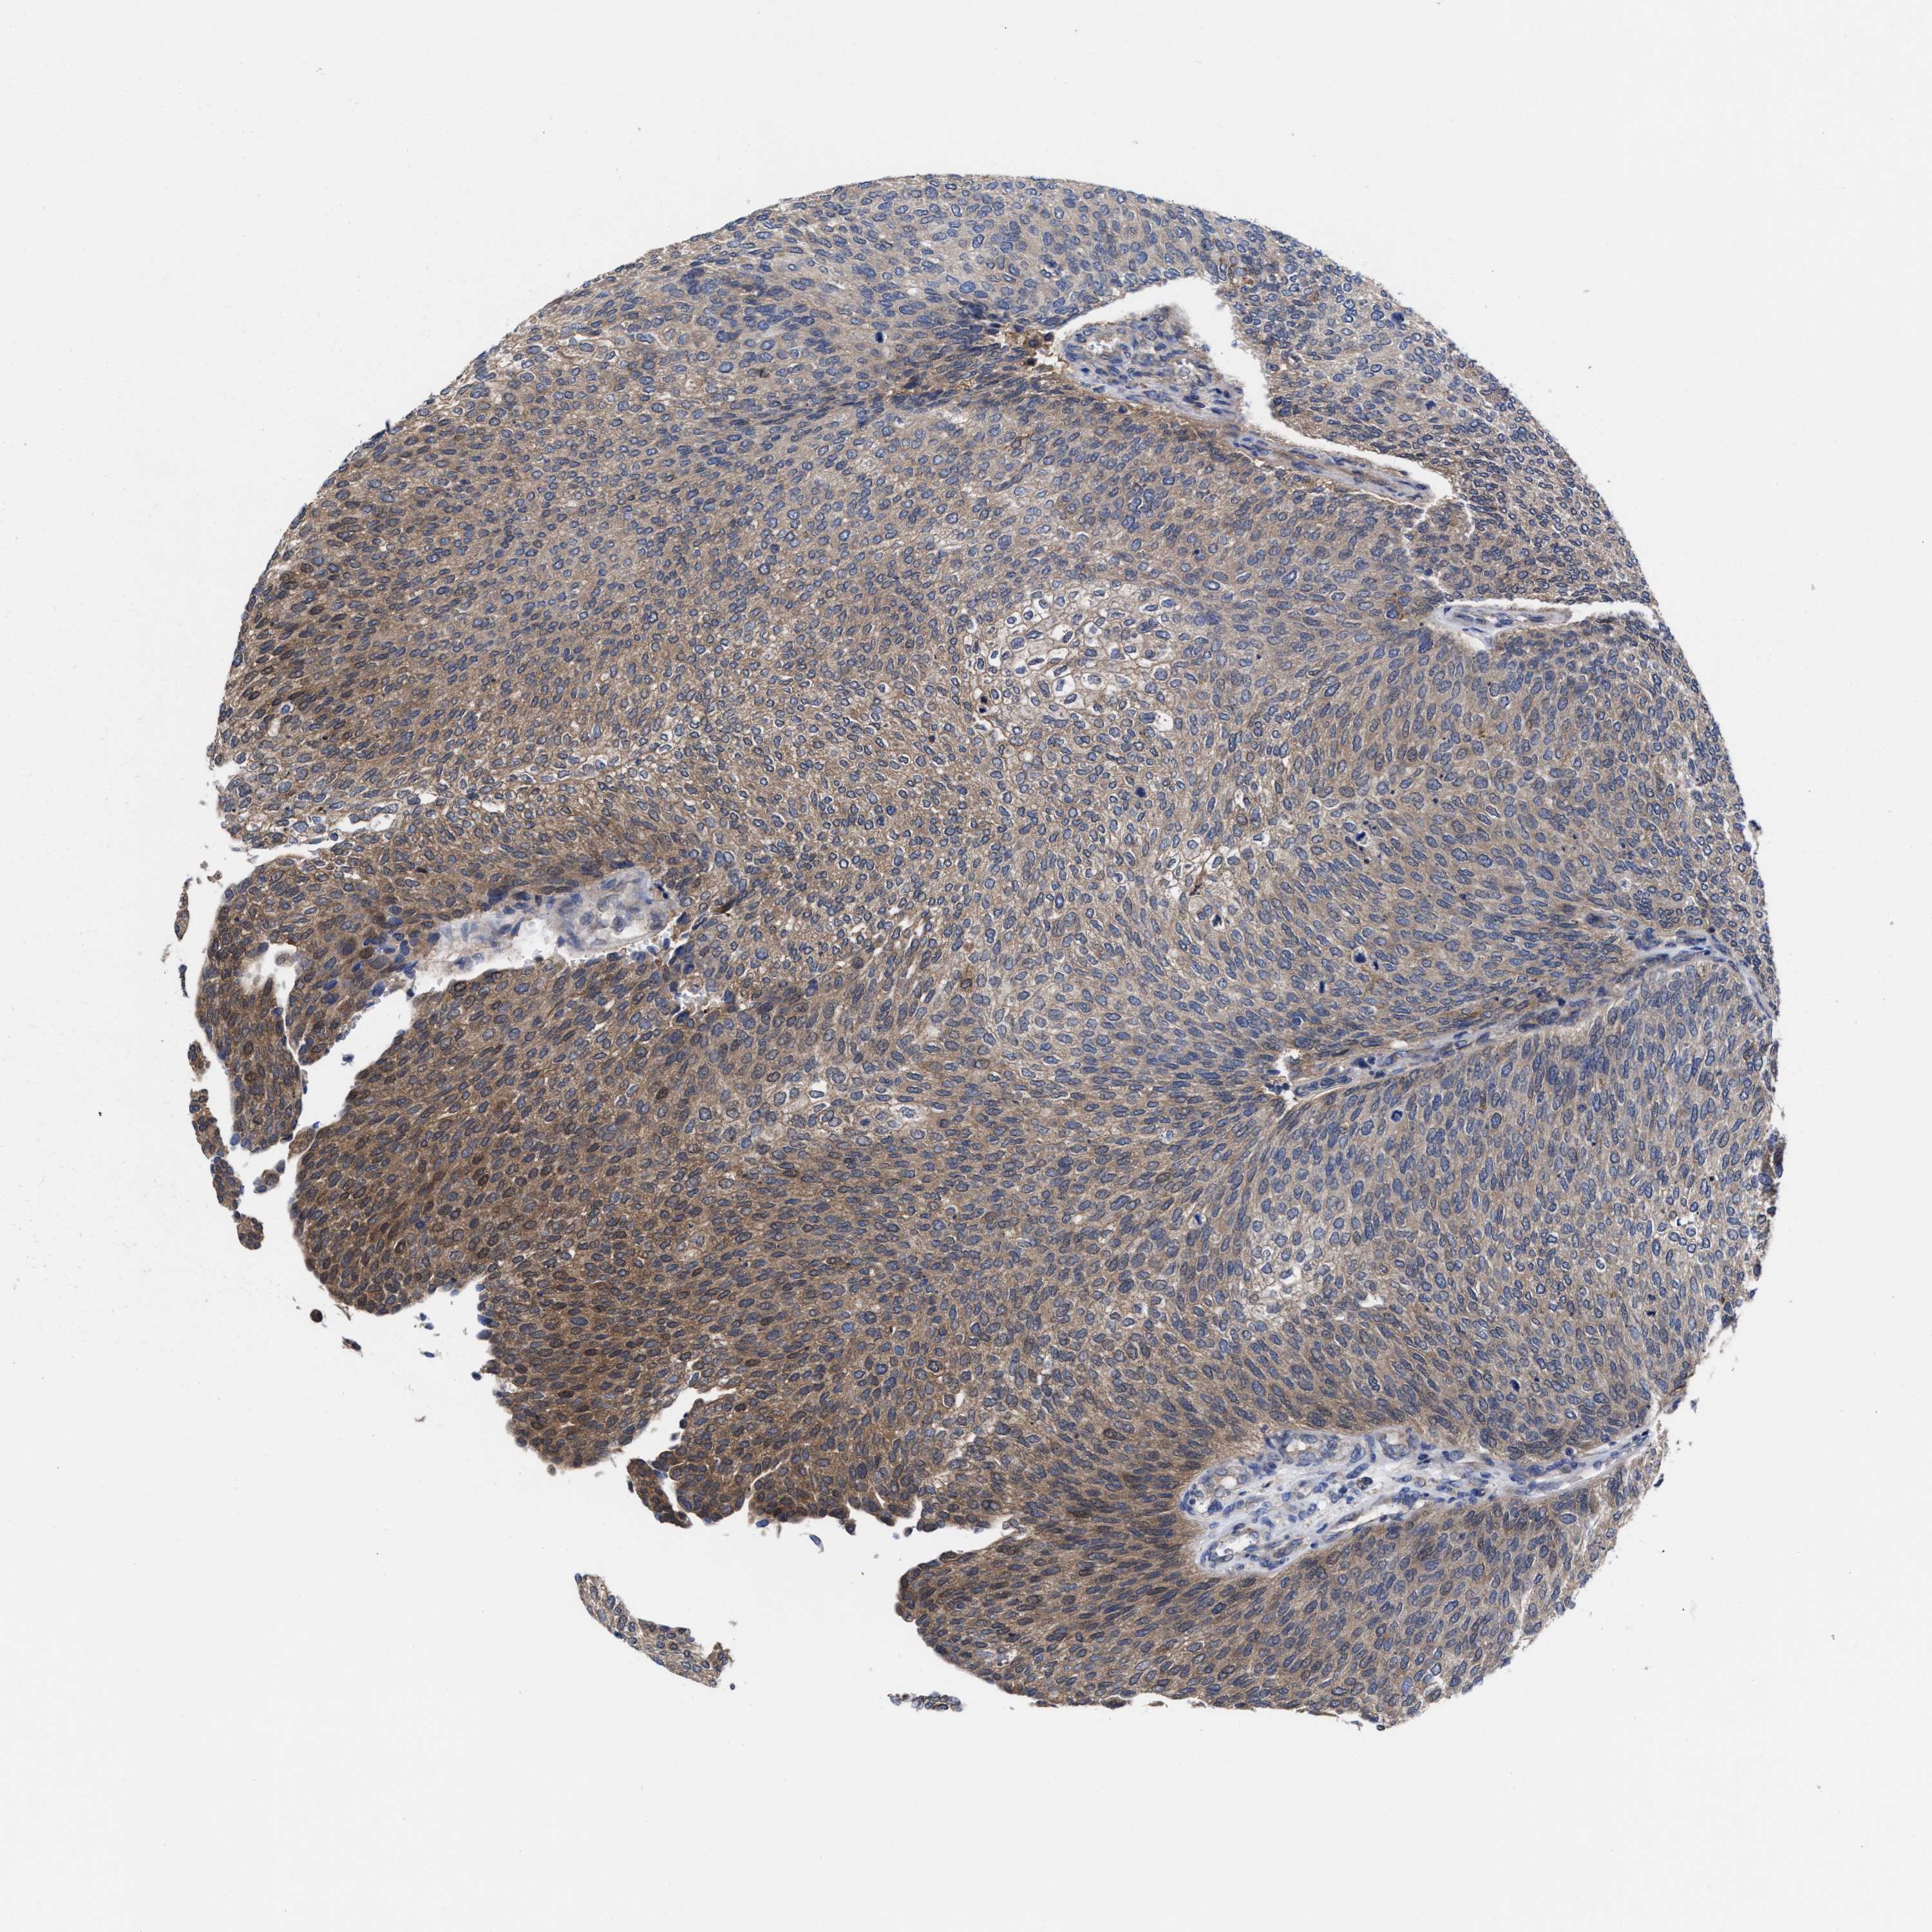

UROTHELIAL CANCER - Protein expressioni

A mouse-over function shows sample information and annotation data. Click on an image to view it in a full screen mode. Samples can be filtered based on level of antibody staining by selecting one or several of the following categories: high, medium, low and not detected. The assay and annotation is described here.

Note that samples used for immunohistochemistry by the Human Protein Atlas do not correspond to samples in the TCGA dataset.

Antibody stainingi

Antibody staining in the annotated cell types in the current human tissue is reported as not detected, low, medium, or high, based on conventional immunohistochemistry profiling in selected tissues. This score is based on the combination of the staining intensity and fraction of stained cells.

Each image is clickable and will lead to virtual microscopy that enables deeper exploration of all samples and also displays staining intensity scores, fraction scores and subcellular localization as well as patient and tissue information for each sample.

Antibody HPA022931

Staining

High

Medium

Low

Not detected

Intensity

Strong

Moderate

Weak

Negative

Quantity

>75%

75%-25%

<25%

None

Location

Nuclear

Cytoplasmic/membranous

Cytoplasmic/membranous,nuclear

Urothelial carcinoma, Low grade

Urothelial carcinoma, High grade